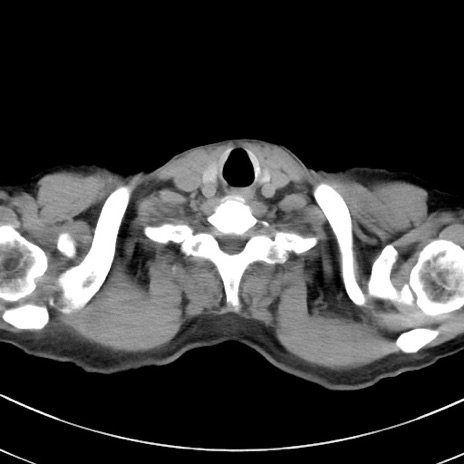

症例38(横断像)

【症例】70歳代 男性

【主訴】腹痛・嘔吐

【現病歴】昨晩より、嘔吐・腹痛あり。今朝になっても嘔吐あり。来院。

【既往歴】心臓バイパス手術、開腹胆摘、腸閉塞

【身体所見】BP 107/71mmHg、HR 116/min、腹部:平坦、軟、下腹部に軽度圧痛あり。反跳痛なし。

【データ】WBC 15100、CRP 0.32